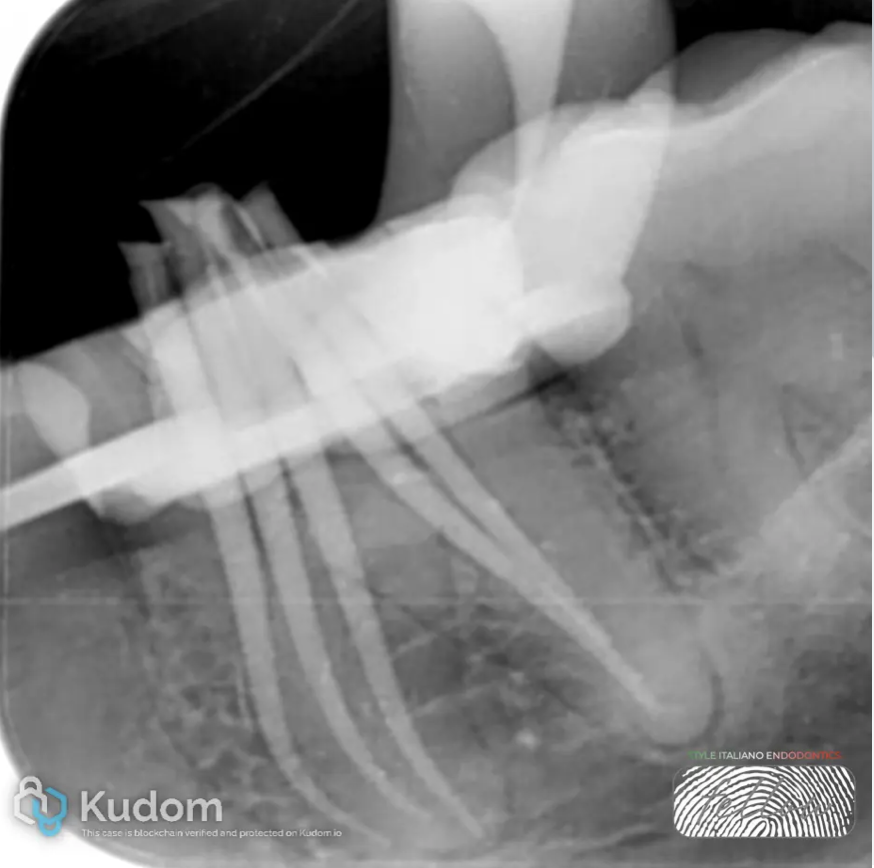

Fig. 1

- Clinical and Radiographic Examination: Tooth 3.6 was evaluated.

- Initial Radiograph

- Diagnosis: Previously treated tooth and Symptomatic Apical Periodontitis.